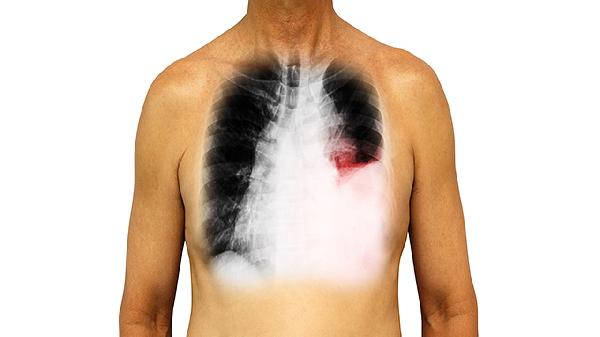

心力衰竭患者需优化强心利尿方案,结核性胸膜炎需规范抗结核治疗6个月以上,恶性肿瘤需评估原发灶控制情况。约60%的肺积水在病因消除后可自行吸收,需定期复查胸片或超声评估疗效。